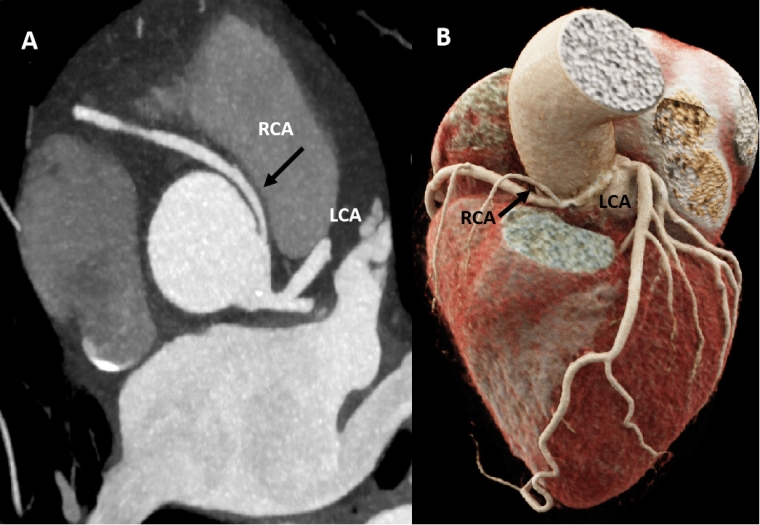

TTE is the most routinely used imaging technique for diagnosis and follow-up. It provides a correct measurement of the aortic root and the proximal ascending aorta, assessing the presence of pathological flows in the aortic arch and, on the other hand, the functionality of the aortic valve [17]. Its main disadvantage is not being able to fully assess the aorta [17].

A global baseline assessment of the aorta, a precise measurement of the maximum diameter, location of the aneurysmal segment and characteristics of its wall can be done with magnetic resonance imaging (MRI) or computed tomography (CT). MRI is generally preferred over CT because of the risk of cumulative radiation exposure; this is especially true for young people who need serial follow-up [23,24]. CT angiography should be considered in case of MRI contraindication and/or prior planning of a surgical or percutaneous intervention.

All patients with an HTAD should undergo at least yearly imaging of the ascending aorta with TTE or MRI, depending on the case. In athletes with BAV or tricuspid valve (TAV) and a non-dilated aorta (<40 mm), follow-up every 2-3 years with TTE is recommended [1,24]. In athletes with BAV or TAV with diameters between 40-45 mm, the frequency of TTE may be either every 1 or 2 years depending on rate of growth [23]. An MRI may also be considered as part of the initial study or in case of discordant measurements by TTE. For patients with an aortic diameter ≥45 mm, a baseline MRI is recommended, along with annual TTE or even more frequently in cases of accelerated growth [24].

Athletes with BAV may present stenosis or insufficiency and its management is similar to that of tricuspid valve disease [1]. When the valvular dysfunction is mild or absent, BAV may go unnoticed during physical examination. ETT is the first-line technique, allowing for an evaluation of the valve morphology and for the presence of potentially associated coronary anomalies to be ruled out [27].

On the other hand, BAV is associated with a small, but increased risk for ascending aortic aneurysm or dissection, and therefore with SCD. As for BAV-associated valvular dysfunction, the impact of ET in aortic dilation is unclear. A single study comparing elite athletes with BAV, non-athletes with BAV and athletes with TAV showed no impact of athletic status on the aortic growth rate. However, studies with larger populations and longer follow-ups are needed to confirm this statement. ETT is again the first-line imaging technique for this scenario, as it allows the evaluation or aortic diameters and to discard BAV-associated aortic coarctation [2]. Aortic MRI and CT complement aortopathy evaluation- as described in the previous section.